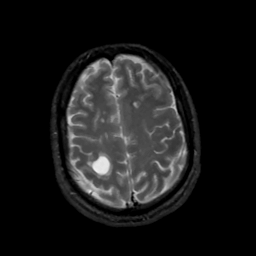

MR Study #5, March 10, 1991 -- Slice #40